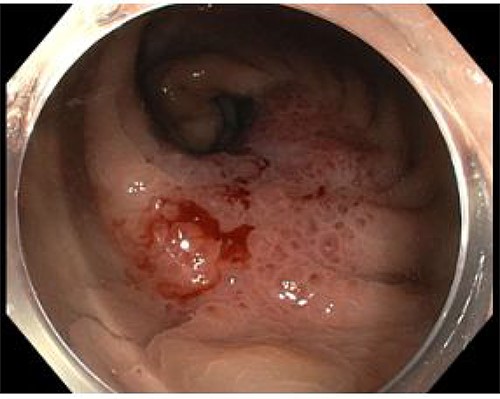

An 82-year-old man with no significant medical history presented with progressive change in bowel habit and abdominal pain for 2 months. Colonoscopy 1 year prior had only revealed diverticulosis but on rectal examination at re-presentation a firm mass was palpable within the rectum. Colonoscopy was repeated and revealed an ulcerated non-obstructing low-rectal mass 3 cm in size (Fig. 1). Biopsies reported adenomatous change with at least high-grade dysplasia and a focus suspicious for invasive adenocarcinoma.

Case A. Endoscopic image at time of initial diagnosis with rectal tumour, prior to neoadjuvant chemoradiation.

The rarity of colorectal metastasis from PDAC and lack of discerning imaging characteristics means radiological reporting is unlikely to suggest a pancreatic primary as the most likely diagnosis. Colonoscopy and biopsy should be performed when possible; the endoscopic appearance may not appear typical of a mucosal lesion such as CRC (Fig. 4). In case B, the presence of large bowel obstruction precluded colonoscopy; synchronous resection was performed due to concern post-operative recovery after right hemicolectomy could significantly delay elective pancreatic resection.